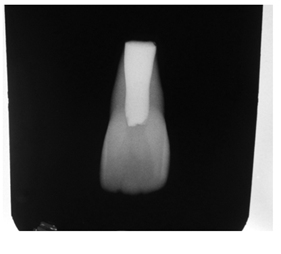

A 10year old boy reported to the department of Pedodontics with a chief complaint of missing upper front tooth and gave a history of fall from bike while 5 days back. They had been to pediatrician for the lacerated lip and got it sutured. Parents had kept the avulsed tooth in paper without knowledge of reimplantation of the same tooth. Patient had no relevant medical and family history. On examination swelling and suture was present on upper lip, lacerated gingiva with healing socket in 11 regions. 21 was intact, vital and non mobile. (Figure 1) (Figure 2) On examination of avulsed tooth 11, it was found to have open apex (Figure 3). On intraoral radiographic examination, no fracture was seen with alveolar bone (Figure 4). Thus avulsed tooth was cleaned and debrided with soft pumice prophylaxis, gentle scaling was done to remove ligament remnants. It was then placed in 1.23% sodium fluoride for 15minutes. Extraoral endodontic therapy was also done using retrograde filling of MTA (Figure 5). Local anesthesia was administered and socket was cleaned, curetted and irrigated to remove clot and debris and 11 was slowly reimplanted in socket. Orthodontic wire – composite splinting was done for 4weeks as the dry storage was more than 60minutes (Figure 6). Systemic antibiotics amoxicillin and doxycycline were prescribed for 5days. The patient was recalled after 1 month and splint was removed. No mobility was present. Again patient was recalled after 2months to check the condition (Figure 7). Again patient was recalled after 6months; tooth had slightly discolored but was not mobile and maintained the space (Figure 8). Patient was happy and contended with the reimplantation of his own tooth without disturbing his original look.

Figure 4 Preoperative radiograph.